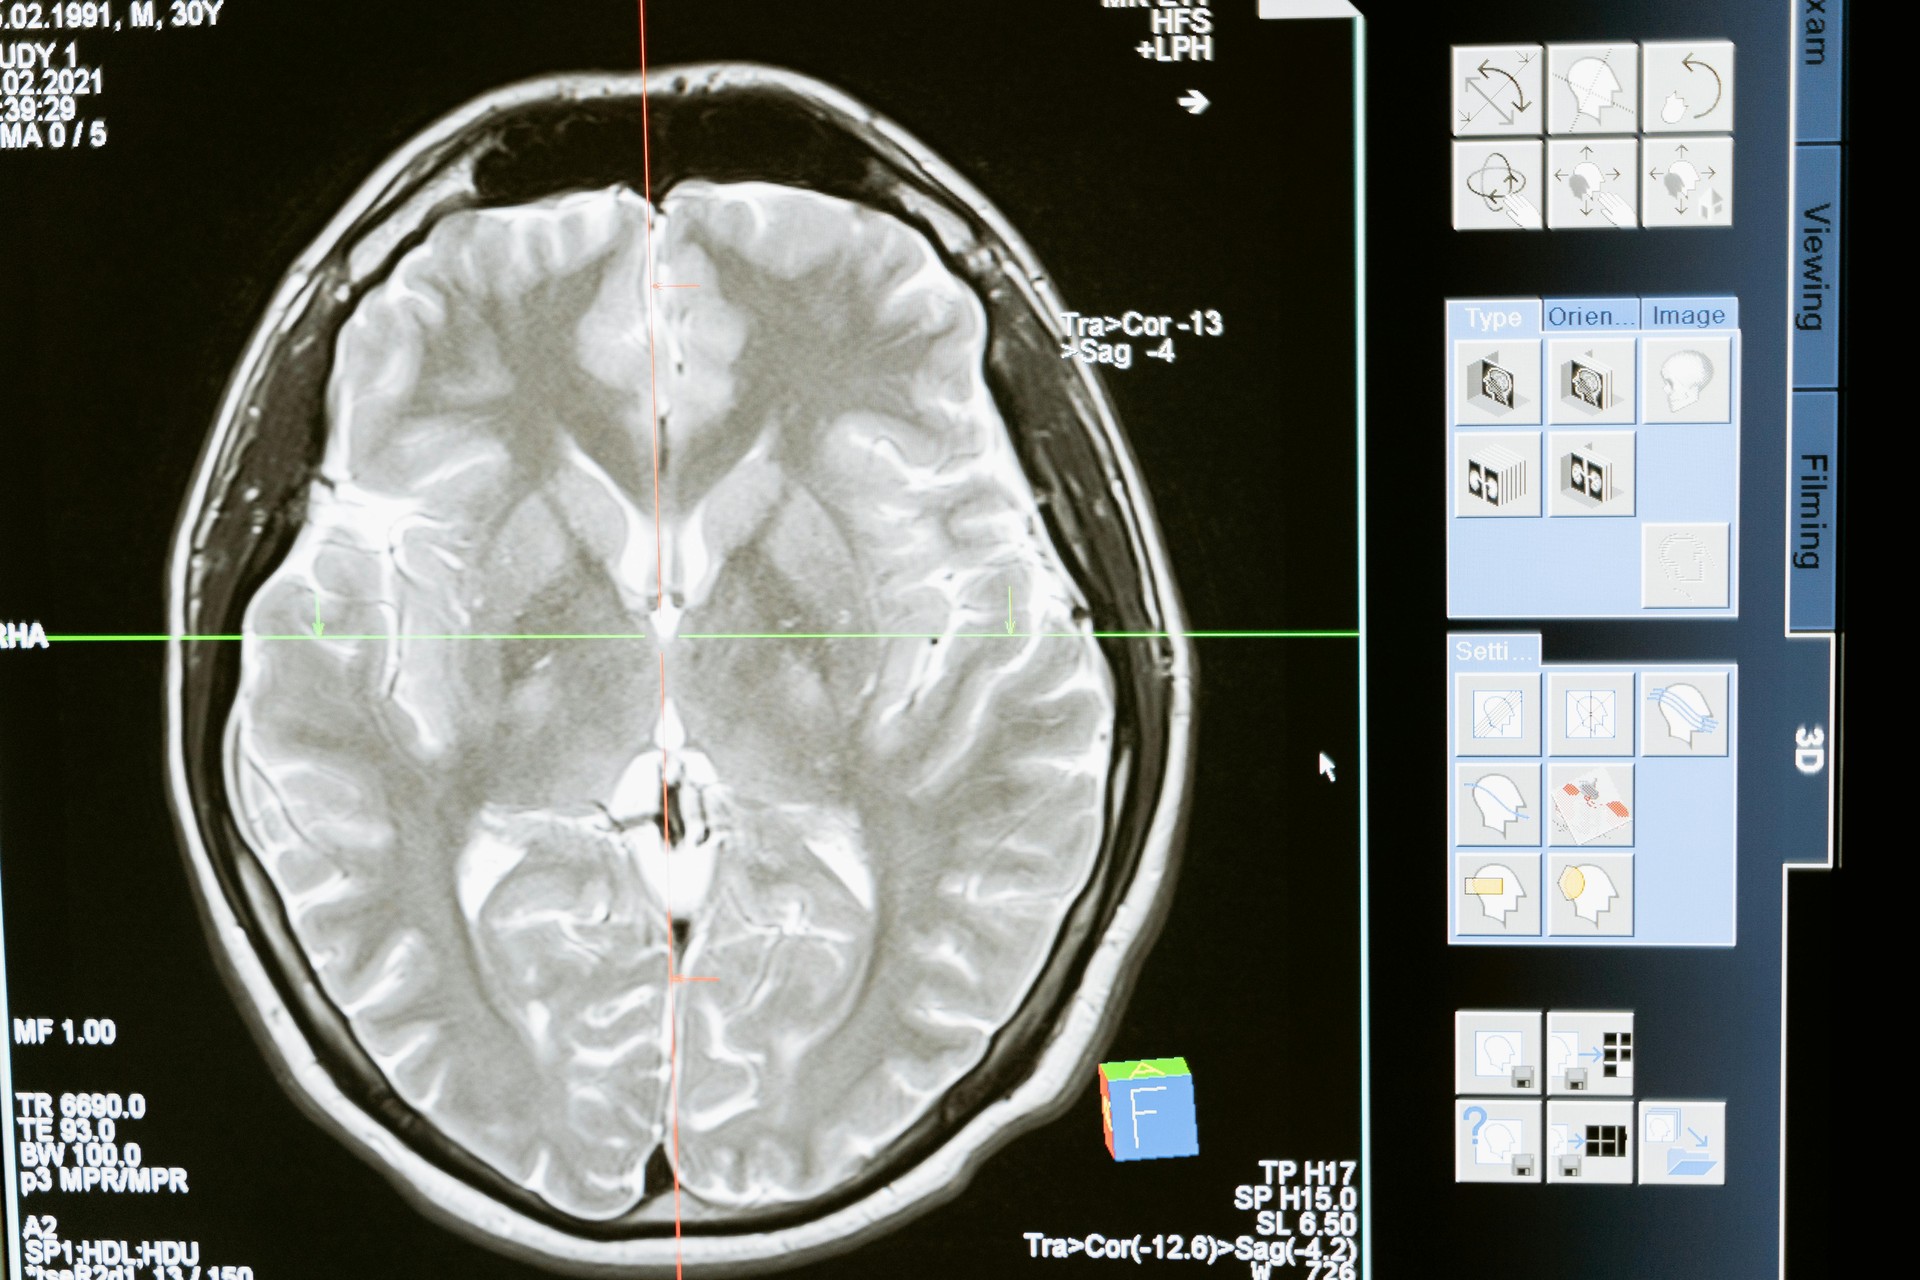

Estos sistemas se entrenan con enormes bases de datos que contienen información de pacientes, como imágenes médicas (radiografías, resonancias, tomografías), historiales clínicos, resultados de laboratorio y datos genéticos. Mediante algoritmos avanzados de machine learning y deep learning, la IA aprende a reconocer anomalías, marcadores de enfermedades y patrones sutiles que podrían pasar desapercibidos para el ojo humano. Por ejemplo, en radiología, la IA puede detectar lesiones minúsculas en una mamografía o un tumor incipiente en una resonancia magnética con una precisión asombrosa.

La IA ya está demostrando su valía en diversas especialidades médicas. En radiología y dermatología, sistemas de IA han logrado una precisión comparable o incluso superior a la de los especialistas humanos en la detección de cánceres de piel y tumores. En oftalmología, la IA ayuda a diagnosticar retinopatía diabética con alta fiabilidad. Mirando al futuro, se espera que la IA impulse la medicina personalizada, permitiendo tratamientos adaptados a la genética y el perfil de cada paciente, y que juegue un papel clave en el desarrollo de nuevos fármacos y terapias.